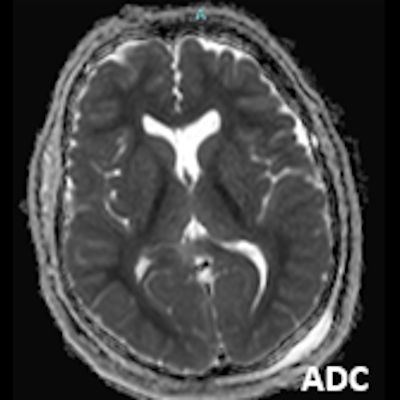

- A) Bilateral serebral kortekste (oklar) ve bazal ganglionlarda (oklar) yaygın DAG hiperintens, ADC hipointens difüzyon kısıtlamaları görülüyor.

- B) 9 gün sonraki difüzyon MR incelemede kortikal ve bazal ganglionlardaki difüzyon kısıtlamalarının gerilediği, bilateral serebral beyaz cevherde (oklar) ve internal kapsül arka bacağı- kortikospinal trakt boyunca (oklar) yaygın DAG hiperintens, ADC hipointens difüzyon kısıtlamalarının geliştiği izleniyor.